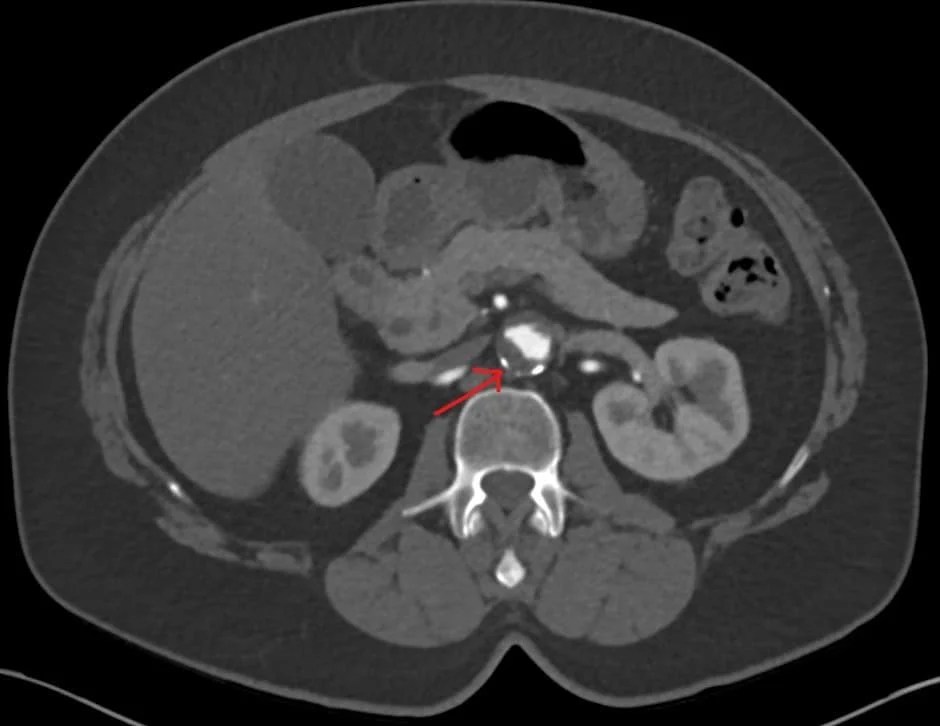

CT angiography revealing massive mural thrombus in the descending Mural Meaning Radiology Antral wall thickness commonly exceeds 5. This is the most concerning etiology. Heterogeneous, focal and asymmetrical mural thickening is suspected for malignancy, while symmetrical and homogeneous thickening is. Crohn disease, also known as regional enteritis, is an idiopathic inflammatory bowel disease characterized by widespread. Smooth wall thickening of the distal gastric antrum relative to the proximal stomach on mdct with. Mural Meaning Radiology.